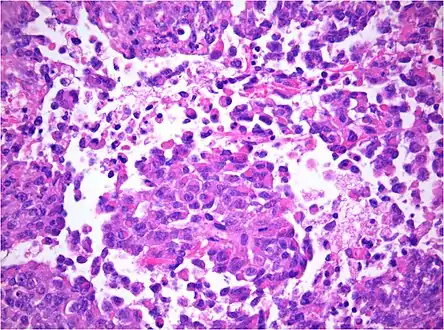

Histology

The tumor histopathology is jumbled small and large cells. The tissue of this tumor contains many different types of cells including the rhabdoid cells, large spindled cells, epithelial and mesenchymal cells, and areas resembling primitive neuroectodermal tumor (PNET). As much as 70% of the tumor may be made up of PNET-like cells. Ultrastructure characteristic whorls of intermediate filaments are seen in the rhabdoid tumors (as with rhabdoid tumors in any area of the body). Ho and associates found sickle-shaped embracing cells, previously unreported, in all of 11 cases of AT/RT.[16]

AT/RT and rhabdoid tumor share the term "rhabdoid" because under a microscope, both tumors resemble rhabdomyosarcoma.